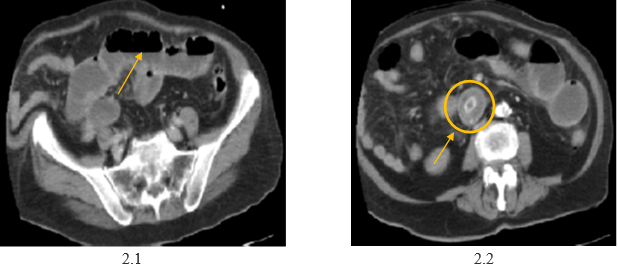

A continuación, se presentan las imágenes y hallazgos de los diferentes estudios imagenológicos solicitados a la paciente en el proceso de diagnóstico y tratamiento.

Foto 2: Corte axial TAC de abdomen y pelvis con contraste. Se evidencia la distensión de asas delgadas (2.1) y sitio de impactación del cálculo biliar (2.2).